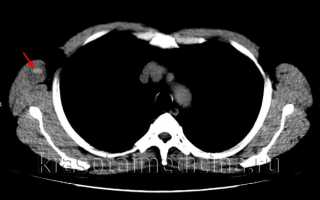

КТ ОГК показывает гиперденсное скопление крови в мышечном массиве грудной стенки справа, окруженное зоной отека.

image